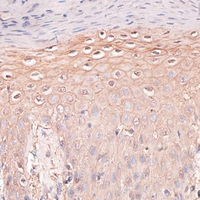

• Immunohistochemical analysis of P Cadherin staining in human skin formalin fixed paraffin embedded tissue section. The section was pre-treated using heat mediated antigen retrieval with sodium citrate buffer (pH 6.0). The section was then incubated with the antibody at room temperature and detected using an HRP conjugated compact polymer system. DAB was used as the chromogen. The section was then counterstained with haematoxylin and mounted with DPX.